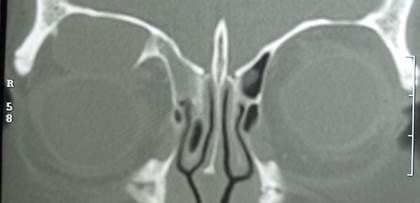

Fractura orbitaria

Las fracturas orbitarias se pueden encontrar aisladas o asociadas a otras fracturas faciales

Cuando afectan solamente las paredes, respetando el reborde orbitario se denominan fracturas puras

Se han propuesto 2 teorías (para tipo blowout): conducción ósea e hidráulica

Los signos clínicos más frecuentes para una fractura de piso tipo blow out en adultos son: equimosis periorbitaria y hemorragia subconjuntival.

5% de los adultos con traumatismo craneoencefálico tienen fracturas orbitarias, y la mitad de ellas requerirán intervención quirúrgica.

Su resolución depende de los síntomas asociados y el tamanio de la misma. Los tratamientos pueden ir desde observación hasta reconstrucción de la fractura con distintos materiales.

Las indicaciones quirúrgicas más comúnmente utilizadas son:

• Diplopía en ortoposición

• restricción a la supra o infraducción dentro de los 30 grados de la visión primaria.

• Confirmación radiológica de fractura mayor del 50% de la pared afectada.

• Enoftalmos mayor a 2mm o cosméticamente inaceptable para el paciente.